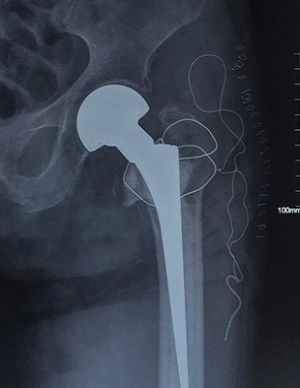

Phẫu thuật thay khớp háng thành công cho cụ bà 95 tuổi

•   22/04/2020 20:26:34

•   Đã xem: 569

Mới đây, các bác sĩ Khoa Ngoại chấn thương chỉnh hình, Bệnh viện Hoàn Mỹ ITO Đồng Nai đã phẫu thuật thay khớp háng thành công cho cụ bà Đ.T.M. (95 tuổi, ngụ tại phường Hố Nai, TP. Biên Hòa).